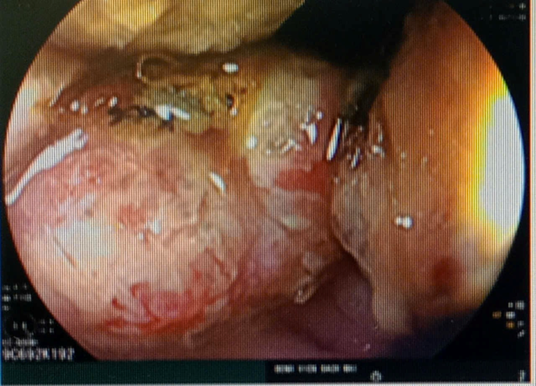

• Chụp cắt lớp vi tính:

Hình 2: Hình ảnh chụp cắt lớp vi tính ổ bụng cho thấy tại vị trí đại tràng lên, đại tràng sigma thành dày không đều quanh chu vi, dày nhất ~ 22mm, trên đoạn dài lần lượt 41mm và 55mm, không rõ cấu trúc lớp, gây hẹp lòng ruột, ngấm thuốc mạnh sau tiêm, kèm thâm nhiễm vài hạch xung quanh, hạch ngấm thuốc sau tiêm, lớn nhất kích thước 8x9mm (>4 hạch)